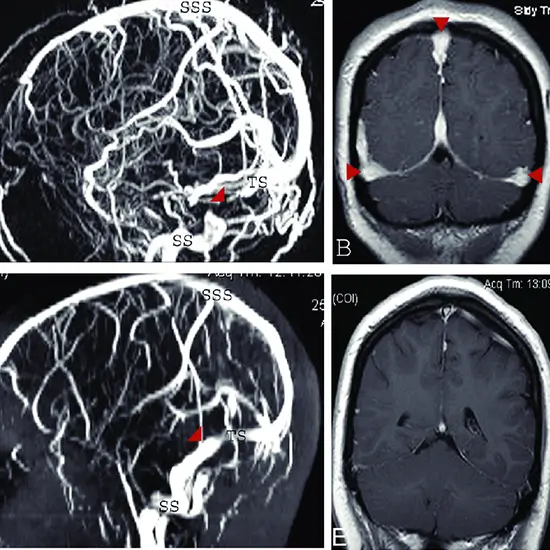

Venography is an x-ray exam that uses a contrast material injection to show how blood flows through your veins. It may be used by your doctor to detect blood clots, identify a vein for use in a bypass procedure or dialysis access, or assess varicose veins prior to surgery.